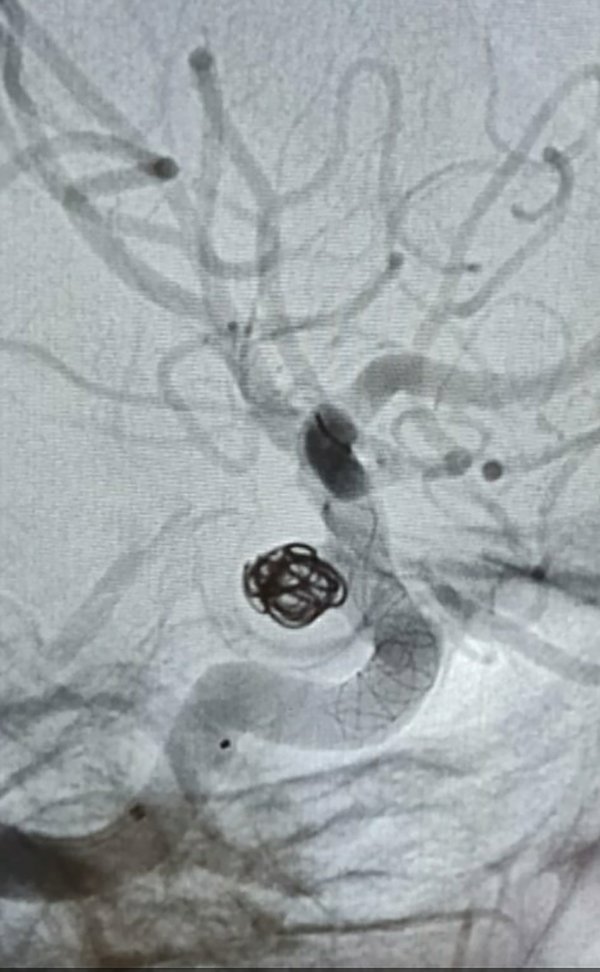

Materiales y métodos: Se presenta una serie de casos, ocho en total, todos con hemorragia subaracnoidea, todos tratados con sistemas diversor del flujo, de diferentes tamaños, se utilizaron los modelos: silk y silk vista baby (balt) pipeline (medtronic), todos implantados en periodo subagudo, es decir a partir de las 48 horas y hasta los 30 días, el más alejado al acontecimiento. Cinco Femeninas, tres masculinos. En dos casos se implantaron adicionalmente al diversor, coils, por el tamaño sacular del aneurisma. A todos se los siguió clínicamente según escala de Rankin modificada y controles inmediatos angiográficos post embolización y angiografía a los 7 meses.